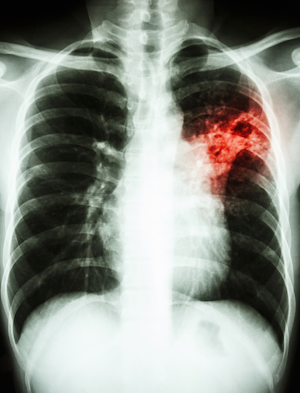

Les poussières de bois les plus fines atteignant le poumon ont des effets sur la santé particulièrement graves : les lésions provoquées sont définitives et peuvent engendrées des maladies respiratoires évolutives et incurables comme la fibrose pulmonaire, qui altère le fonctionnement des poumons, entraîne une détresse respiratoire de manière définitive et réduit considérablement l'espérance de vie. Elles restent néanmoins relativement rares, contrairement aux cancers qui, eux, représentent 80% des maladies professionnelles reconnues comme étant liées aux poussières de bois et peuvent se révéler plusieurs dizaines d'années après l'exposition 5.